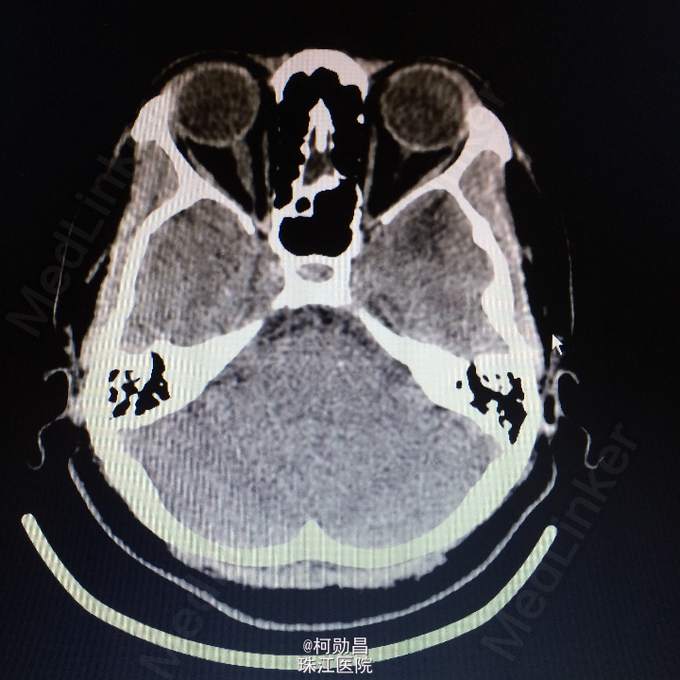

间断性眩晕伴头痛10余年 患者10年来无明显诱因间断性出现起床后眩晕,为天旋地转状,伴头痛、恶心、呕吐,严重时会出现肢体抽搐,双眼紧闭,无口角抽搐、意识障碍等。大约每年发作一次,数小时后自行好转,自服药物治疗(具体不详)。患者1个月前再次出现上述症状,遂至我院诊治:查头颅MR提示:左侧颞极前部皮层及皮层下异常信号影,不排除肿瘤。建议增强扫面。

查体:神经系统查体未见明显异常 头颅CT:左颞极前部占位,建议增强检察 头颅MR:左侧颞极前部皮层及皮层下异常信号影,不排除肿瘤。

诊断:脑膜血管瘤 处理:开颅手术切除,术后病理提示:(左颞极)脑膜血管瘤